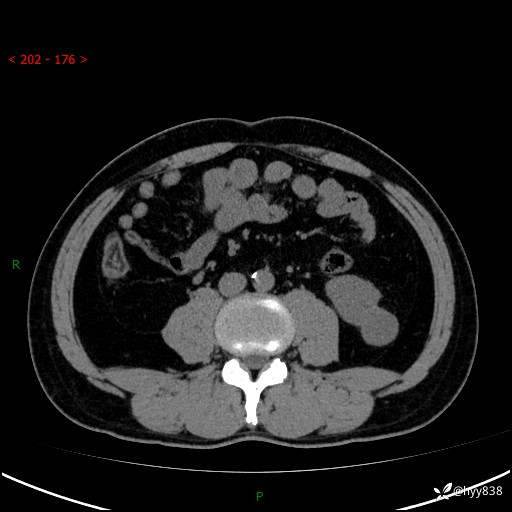

中年男性,左侧腰背部间断性胀痛不适。第一眼“乳头或囊肿”,有无意外---(有结果)

【患者信息】:41岁/男

【主诉】:左侧腰背部间断性胀痛不适1周

【现病史及既往史】:患者1周前无明显诱因出现左侧腰部疼痛,呈间断性胀痛,休息后可缓解,无放射痛,偶可见肉眼血尿,无血块,无尿频尿急尿痛,无夜尿增多,无畏寒发热、咳嗽咳痰等症状。于我院查双肾CT示:左肾占位性病变,左肾下极囊性病变,左肾轻度积水,胆囊多发结石。今为求进一步诊治来我院,门诊以“左肾占位性病变”收治入院。 起病以来,患者精神佳,饮食、睡眠良好,大便正常,小便如上诉,体力体重无明显变化。

【检查】:肾脏CT平扫+增强